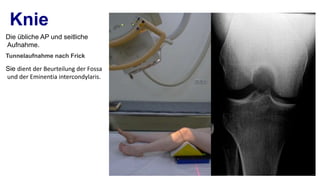

Das Leitbild der „Speziellen Unfallchirurgie“ basiert auf dem Leitbild für das Fach „Orthopädie und Unfallchirurgie“: „Orthopädie und Unfallchirurgie umfasst die Vorbeugung, Erkennung, konservative und operative Behandlung, Nachsorge und Rehabilitation von Verletzungen aller Art und deren Folgen sowie von angeborenen und .Digitales Röntgen des gesamten Bewegungsapparates.sehr freundlich, mit Röntgen, Diagnose und Gespräch in einer Stunde fertig – perfekt.Spezielle Unfallchirurgie Alles in einem Buch: Kompakte und herstellerunabhängige Darstellung der Speziellen Unfallchirurgie.Diagnostik! Die Röntgen-Technik wurde stetig weiterent wickelt und die Strahlendosis immer weiter reduziert: Nach den ersten einfachen Röntgenaufnahmen und der Durchleuchtung unmittelbar am Leuchtschirm wurde die Film-Folien-Technik entwickelt, die trotz geringerer Dosis ein deutlicheres und speicherfähiges Bild ermöglicht. Zur Diagnose nutzen . und laterale Röntgenaufnahme des Knies mit proximaler Tibia beinhalten.